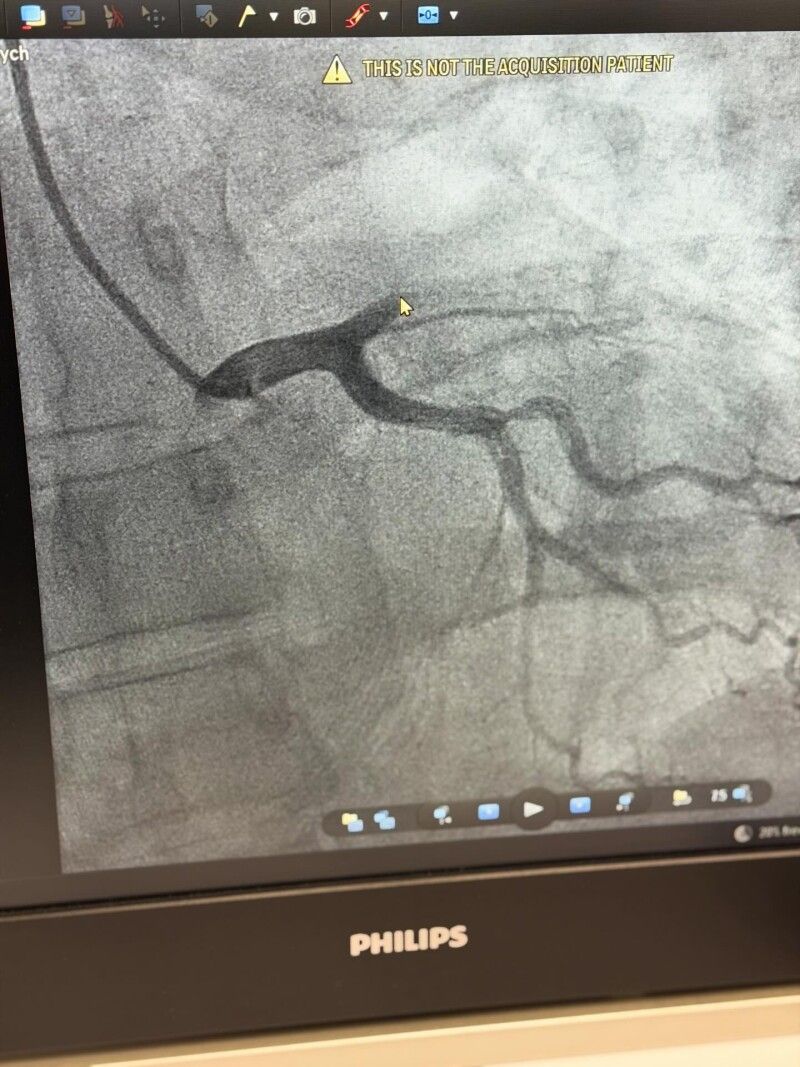

Біль посилювався під час фізичного навантаження, що є характерною ознакою стенокардії. Попри фізичну роботу, пацієнт не проігнорував симптоми й вчасно звернувся по медичну допомогу. Після обстеження було проведено коронарографію, під час якої виявлено оклюзію великої магістральної коронарної артерії.

Пацієнту негайно виконано стентування, що дозволило відновити кровотік у ураженій судині та запобігти подальшому ушкодженню серцевого м’яза.